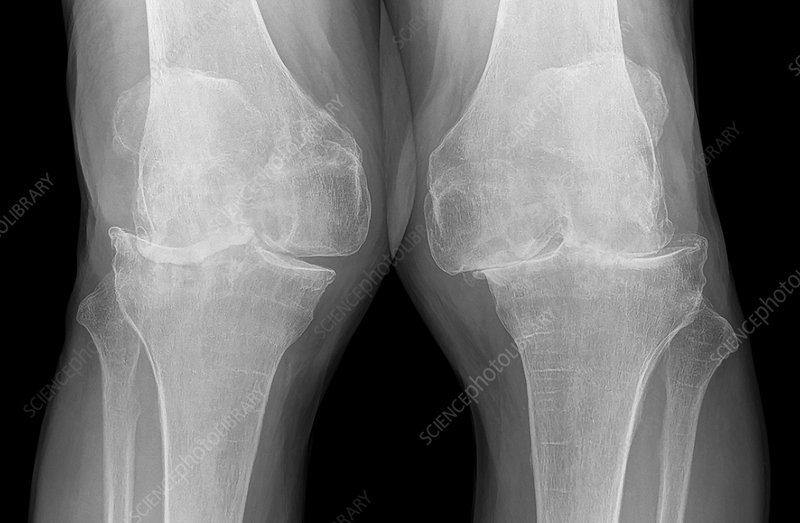

• What pathology is this

Osteoarthritis

• Appearances on xray images for OA

Joint space narrowing

change in appearance of cortical outline

osteophyte formation